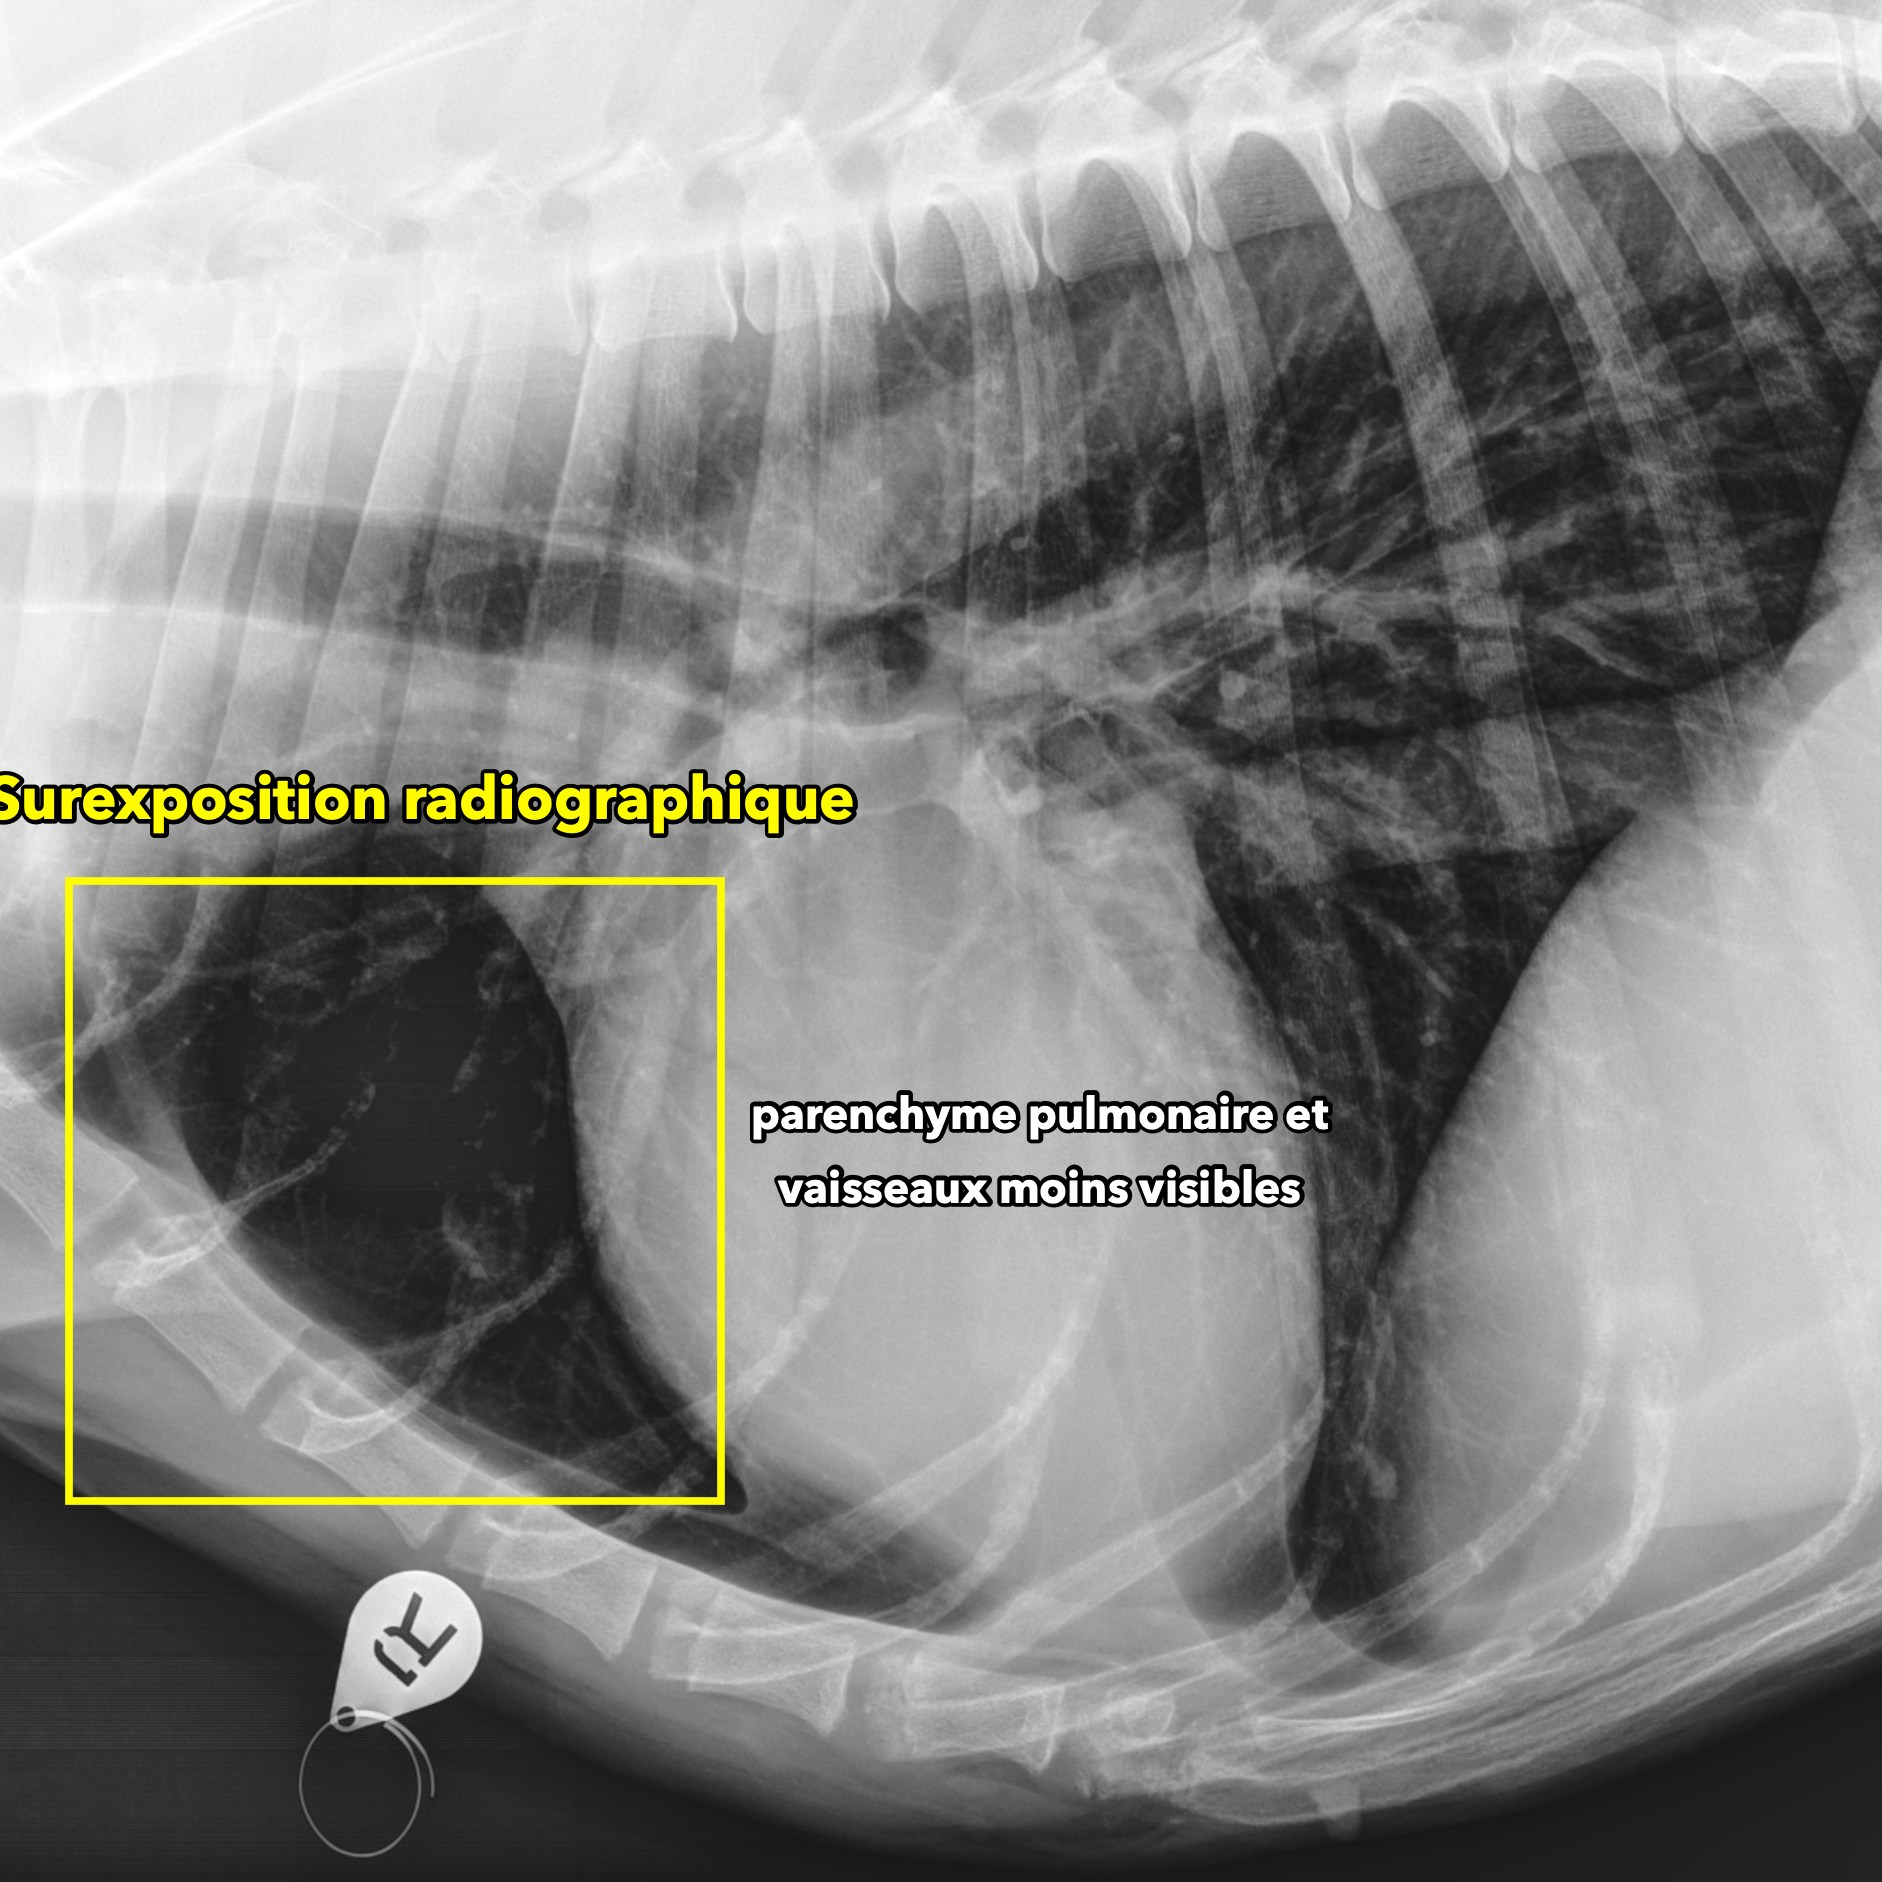

Outre ce positionnement, il faut aussi souligner l’importance de la qualité des images numériques reçues. En effet, ce n’est pas parce que l’animal est bien positionné que l’image radiographique sera forcément optimale pour l’interprétation. La perception subtile des structures normales et anormales peut être grandement affectée lors d’exposition inadéquate ou lorsque le système numérique (ou l’appareil qui émet les rayon-X) n’est pas optimal (problème de calibration, fluctuation de courant, plaque à faible sensibilité aux rayons-X ou à faible résolution).

Les images ci-bas suivantes mettent en relief certains de ces problèmes. Une sous-exposition radiographique (ex. kVp et/ou MAs trop bas pour la région imagée) aura pour effet de limiter la pénétration des structures plus denses (ex. os, voir image #1). Aussi, un nombre insuffisant de rayons-X atteignant le détecteur (plaque numérique) produira davantage de bruit sur l’image qui sera alors affectée. Le résultat sera une image plus granulaire, similaire à si vous aviez pris une photo de nuit avec votre vieil iPhone. Une telle granularité peut aussi apparaître si la plaque numérique est peu sensible (voir image #2), même à exposition adéquate.

Une sur-exposition aura pour effet de « brûler » certaines zones peu épaisses ou de faible atténuation radiographique comme les poumons, faisant disparaître tout détail dans la zone affectée (voir images #3 et #4).